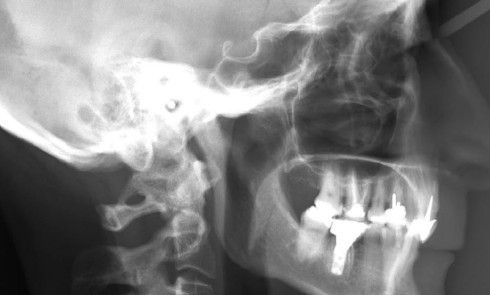

Article réservé à nos abonnés Alternative thérapeutique pour une classe II.2 hypodivergente chez l’adulte : distalisation maxillaire avec minivis

Grand Prix éditorial de l’Orthodontiste et Orthoplus 3e lauréat, catégorie adultes Dans le cas de classe II division 2, dysmorphie souvent associée...